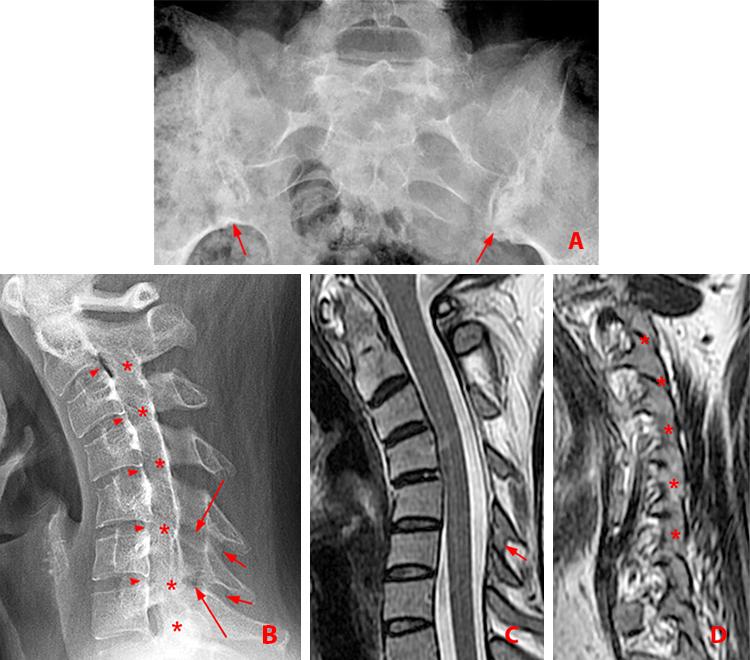

Learning Radiology Dagger Sign, Ankylosing Spondylitis

Ankylosing spondylitis x ray wikidoc Ankylosing Spondylitis X Ray Si Joint Early changes of sacroiliitis (inflammation of the sacroiliac joints) are not. Dosing informationwatch videos for hcps Ankylosing spondylitis often affects the sacroiliac or si joint, which may cause pain in the lower back or buttocks. Imaging is an integral part of the management of patients with ankylosing spondylitis and axial spondyloarthritis. Typical appearance of bamboo spine with multiple syndesmophytes between. Ankylosing Spondylitis X Ray Si Joint.

Learning Radiology Dagger Sign, Ankylosing Spondylitis Ankylosing Spondylitis X Ray Si Joint Dosing informationwatch videos for hcps It typically affects your sacroiliac joint, where your spine and pelvis meet. Early changes of sacroiliitis (inflammation of the sacroiliac joints) are not. Typical appearance of bamboo spine with multiple syndesmophytes between the vertebral bodies are seen. Ankylosing spondylitis often affects the sacroiliac or si joint, which may cause pain in the lower back or. Ankylosing Spondylitis X Ray Si Joint.